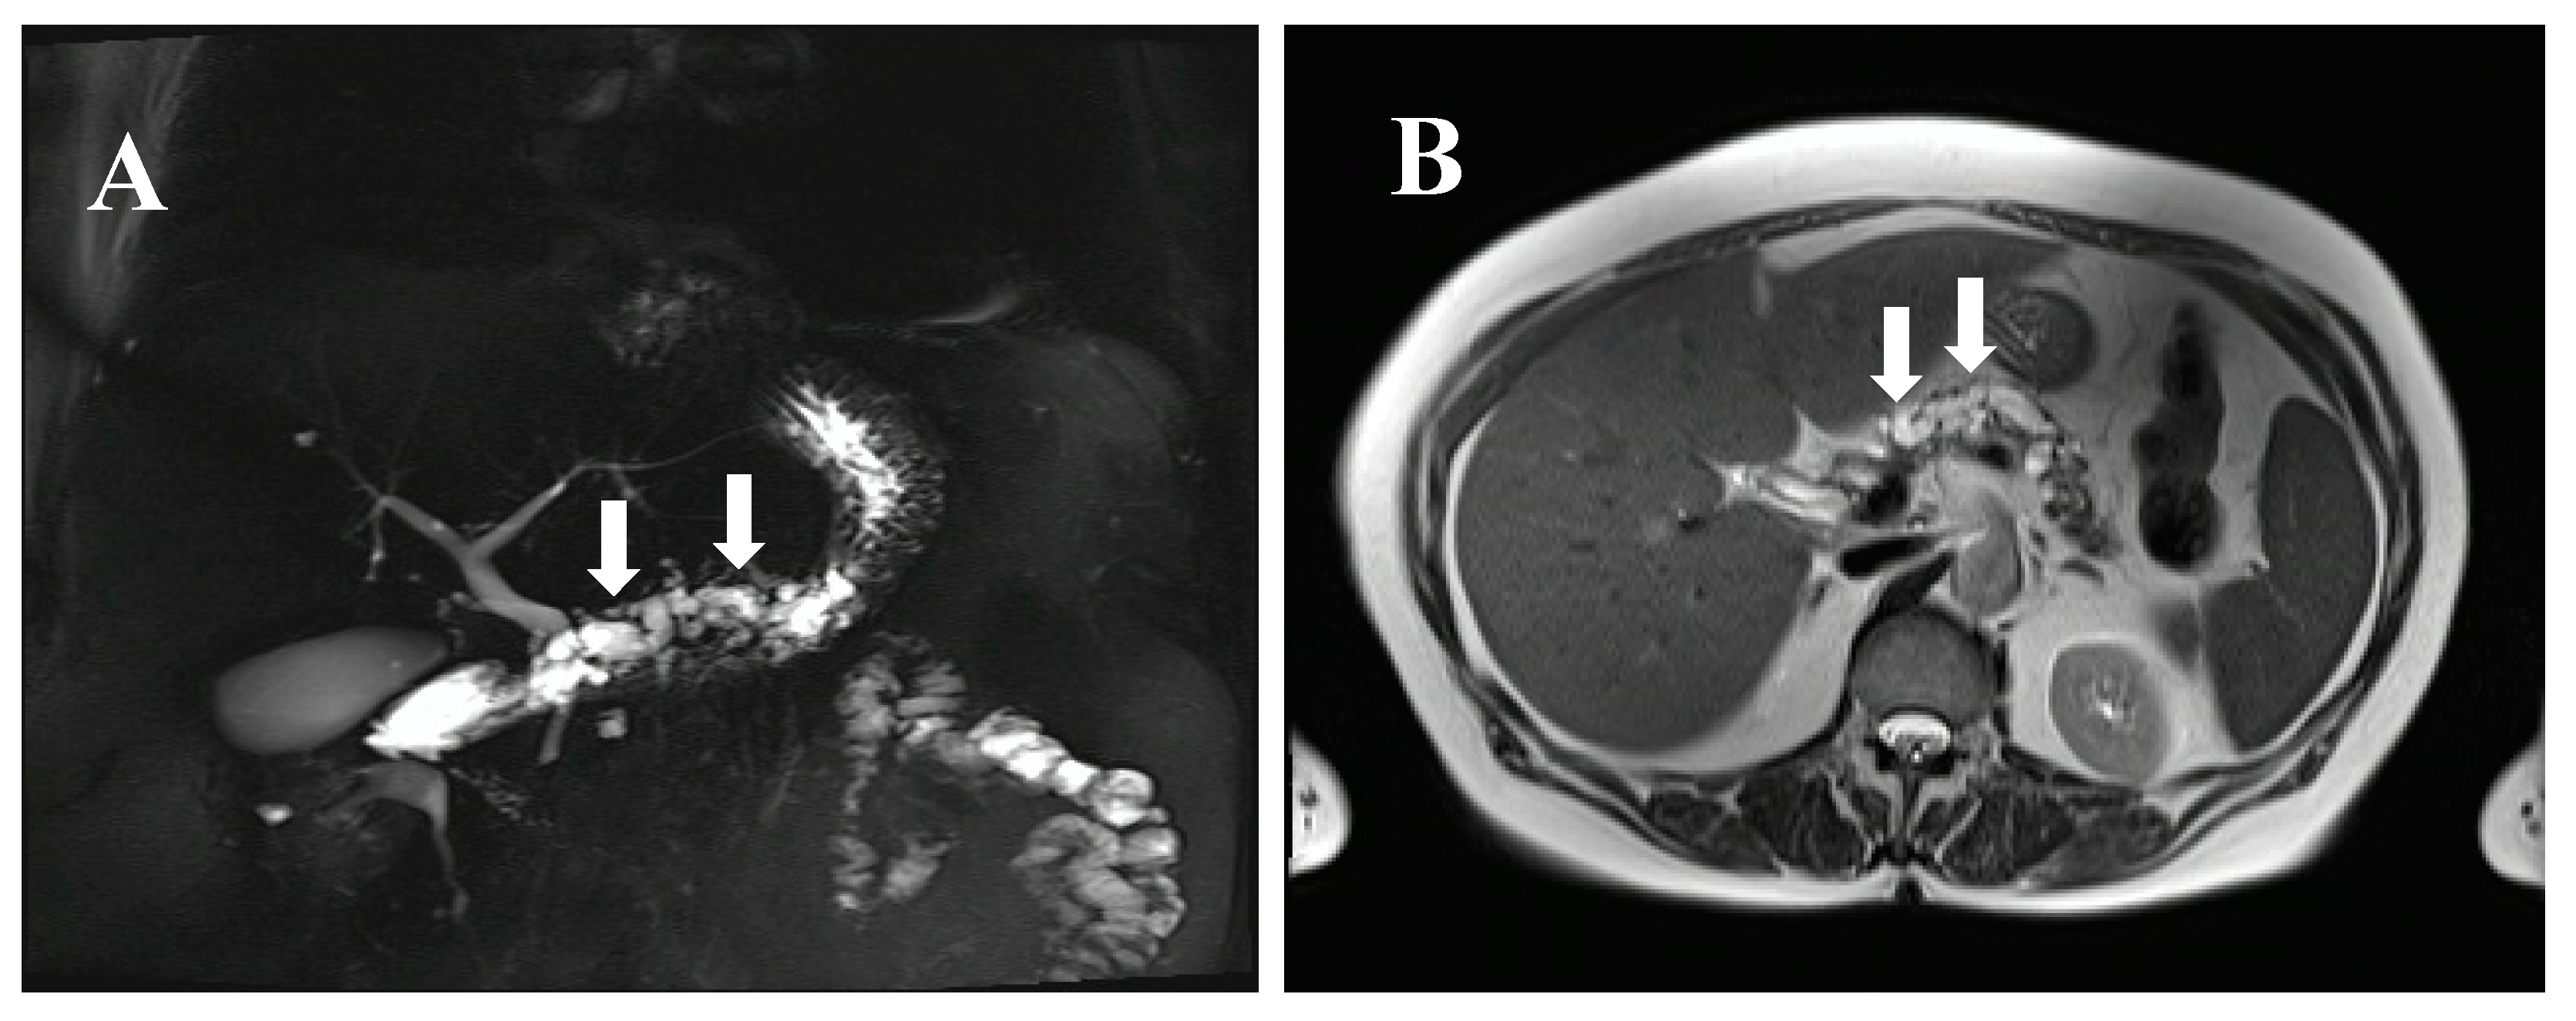

- Bartsch, D.K.; Dietzel, K.; Bargello, M.; Matthaei, E.; Kloeppel, G.; Esposito, I.; Heverhagen, J.T.; Gress, T.M.; Slater, E.P.; Langer, P. Multiple small “imaging” branch-duct type intraductal papillary mucinous neoplasms (IPMNs) in familial pancreatic cancer: Indicator for concomitant high grade pancreatic intraepithelial neoplasia? Fam. Cancer 2013, 12, 89–96. [Google Scholar] [CrossRef] [PubMed]